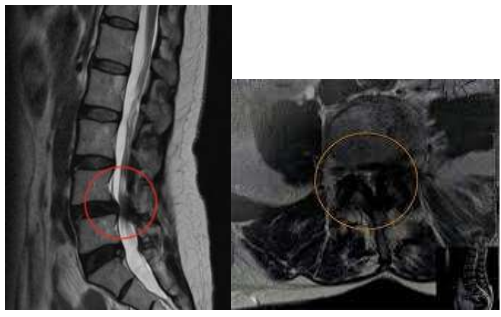

Foi internado em enfermaria da Neurocirurgia, fez tomografia computadorizada (TC) de crânio que foi normal

para a idade, TC e ressonância magnética (RM) de toda coluna que mostrou estenose importante de canal

vertebral na altura de L4, algumas alterações degenerativas discretas no restante da coluna, incluindo a cervical

e sem sinais de fratura vertebral.